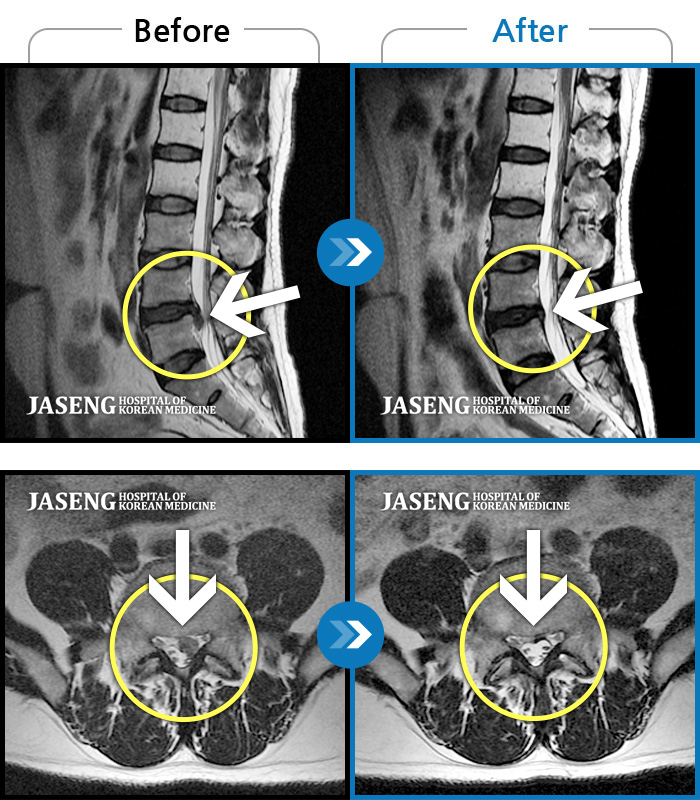

[뱸] 19.11.28~25.05.06